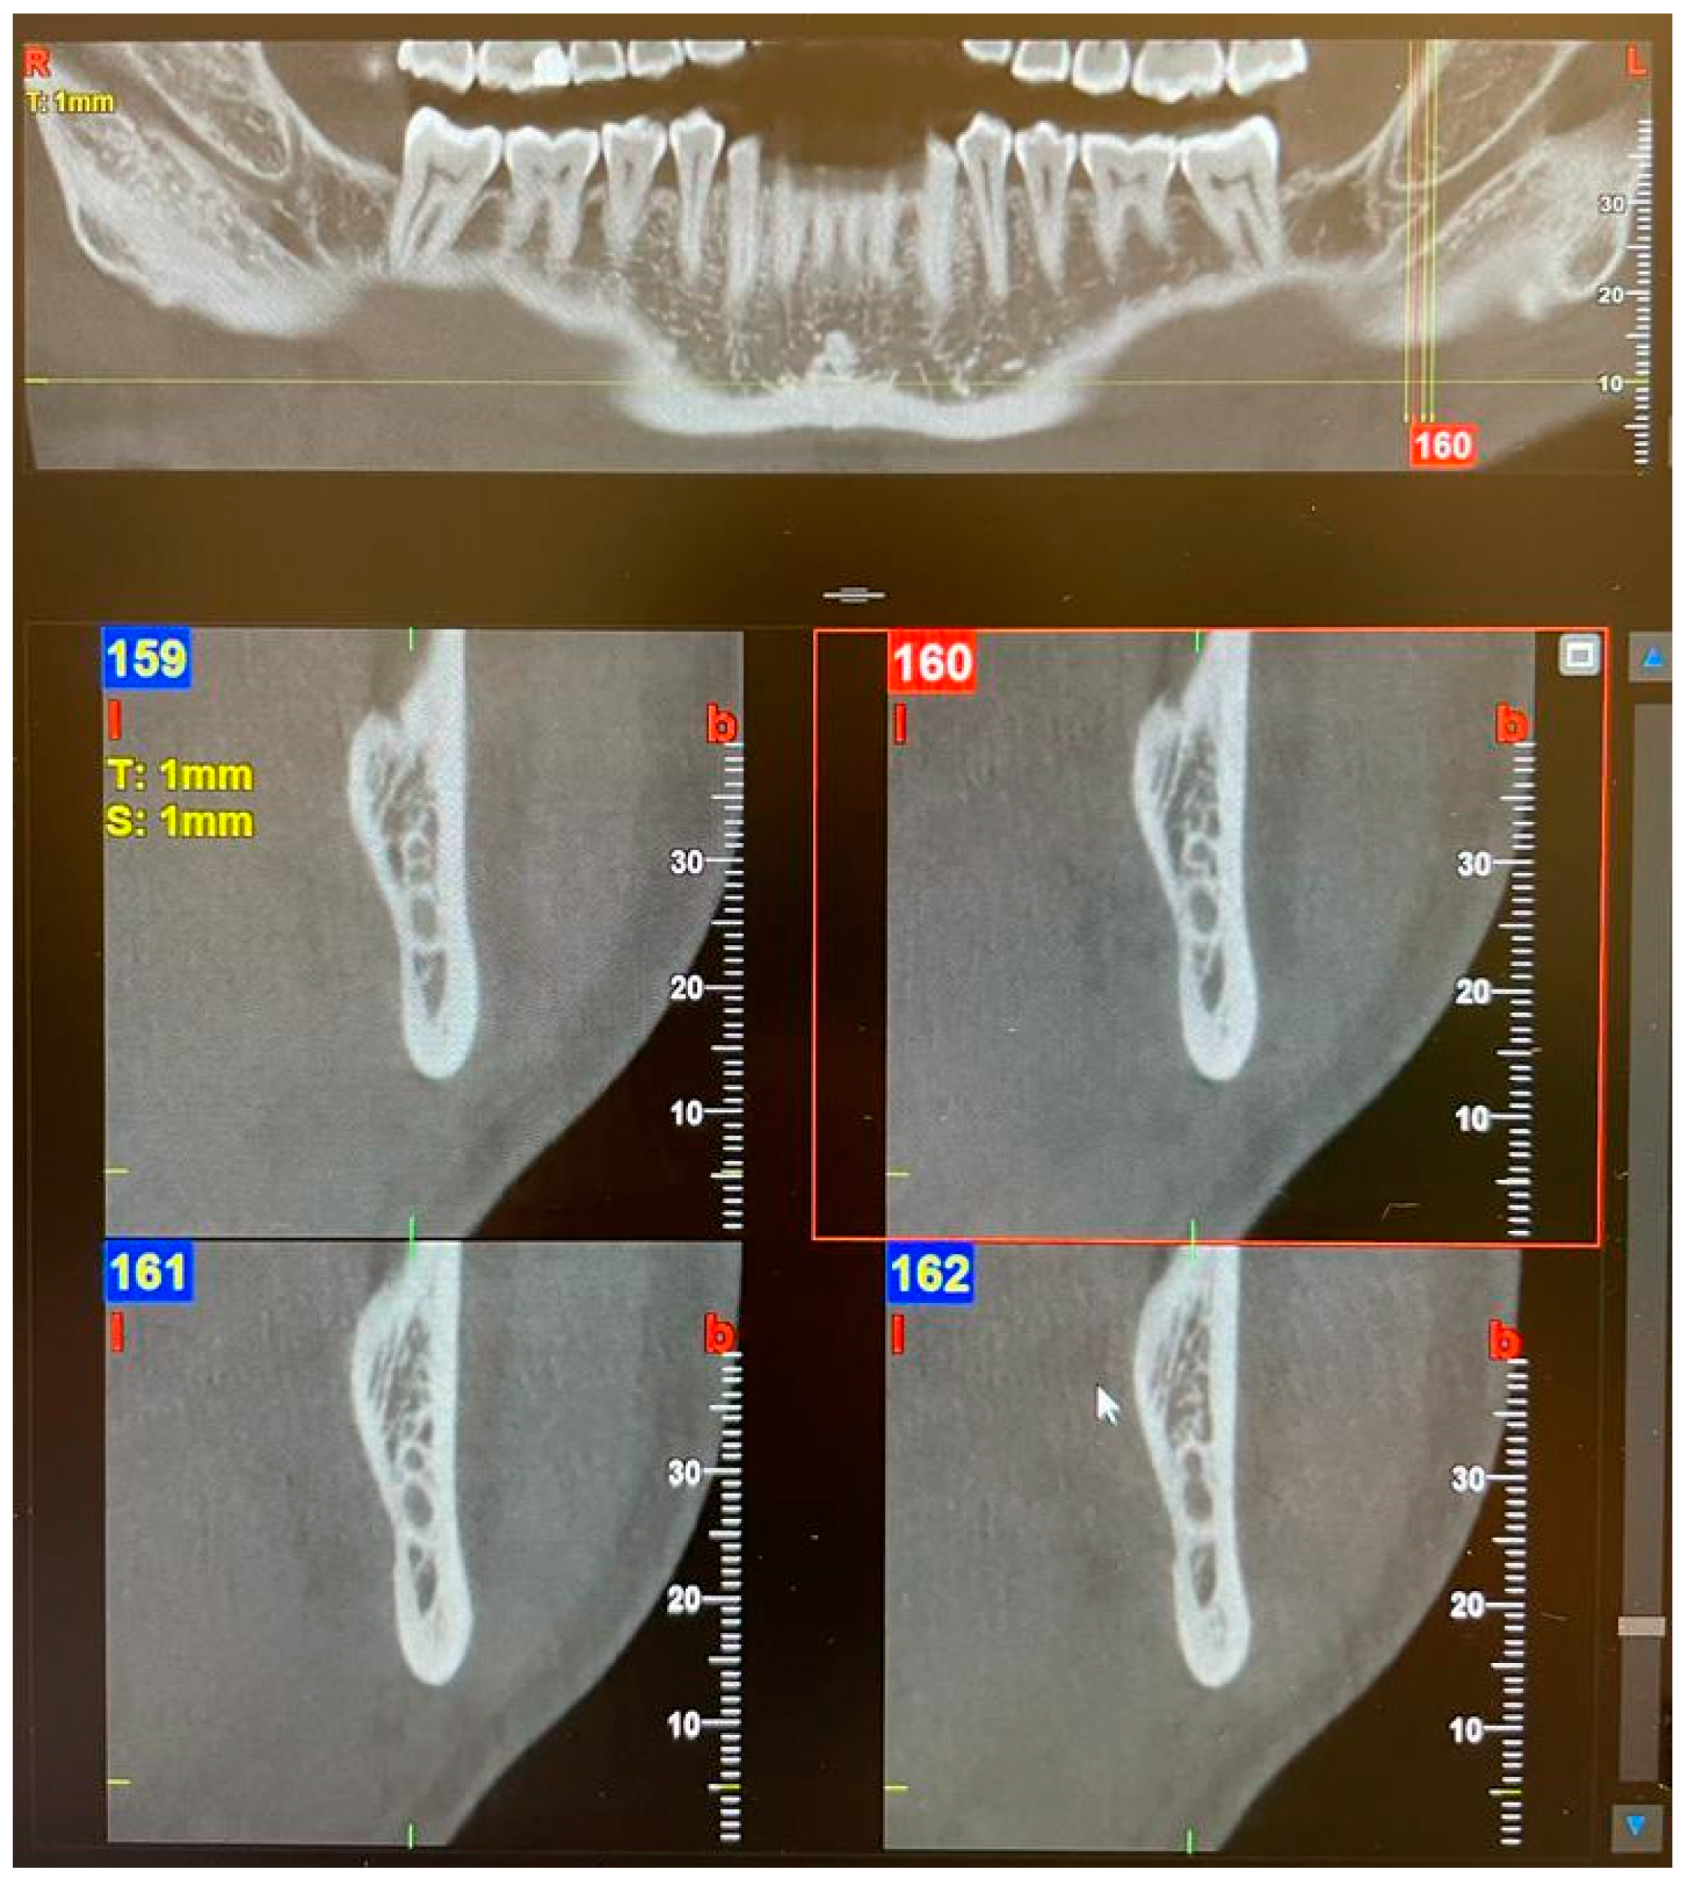

| 1—Retromolar | The retromolar canal, which bifurcates from the mandibular canal in the mandibular ramus region, courses forward, reaching the retromolar region. |